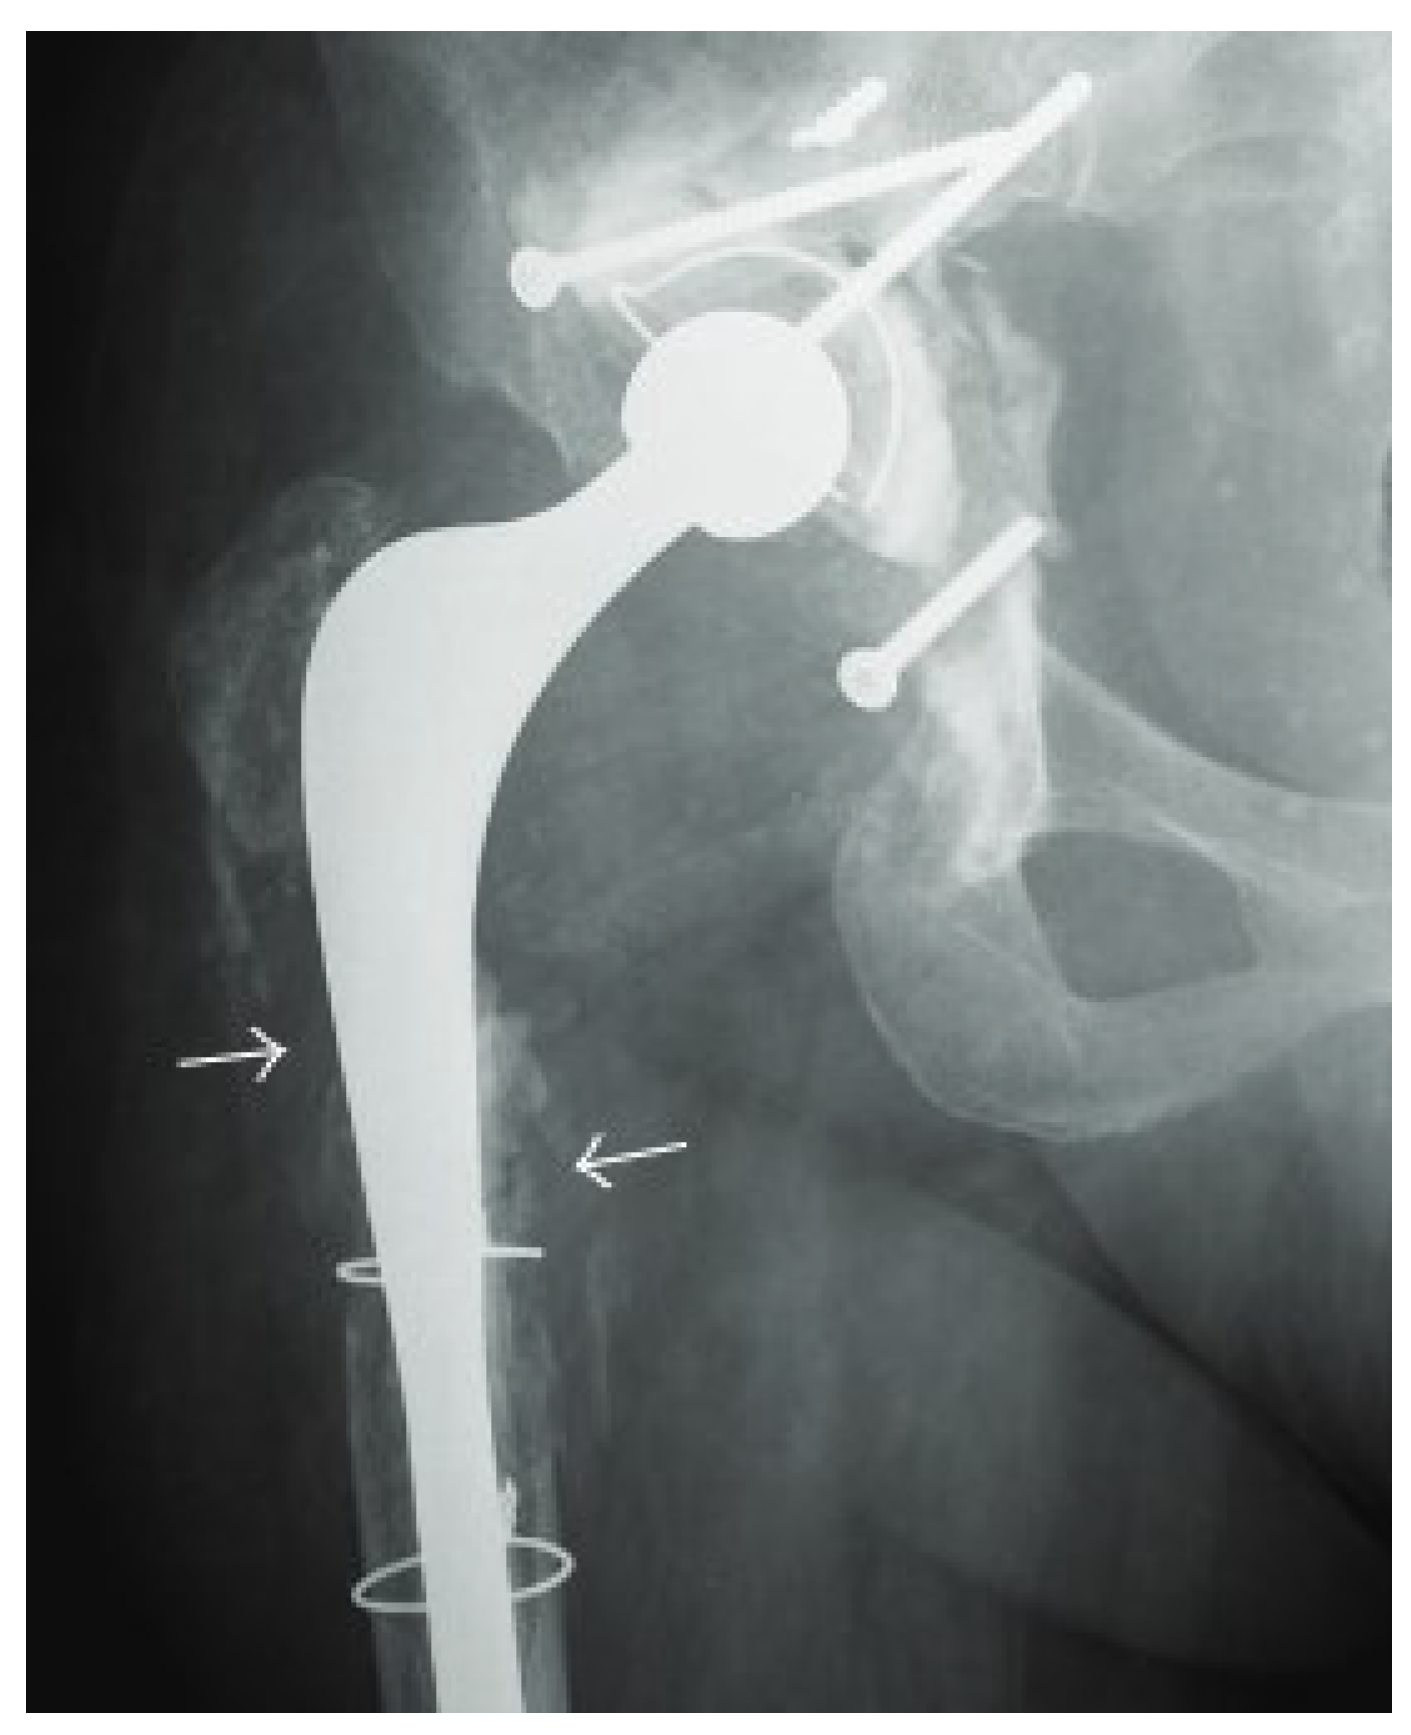

4.1. Radiography

- Hofmann, U.K.; Eleftherakis, G.; Migliorini, F.; Fink, B.; Mederake, M. Diagnostic and prognostic relevance of plain radiographs for periprosthetic joint infections of the hip: A literature review. Eur. J. Med. Res. 2024, 29, 314. [Google Scholar] [CrossRef]

- Li, N.; Kagan, R.; Hanrahan, C.J.; Hansford, B.G. Radiographic evidence of soft-tissue gas 14 days after total knee arthroplasty is predictive of early prosthetic joint infection. Am. J. Roentgenol. 2020, 214, 171–176. [Google Scholar] [CrossRef] [PubMed]

- Weissman, B.N.; Palestro, C.J.; Fox, M.G.; Bell, A.M.; Blankenbaker, D.G.; Frick, M.A.; Jawetz, S.T.; Kuo, P.H.; Said, N.; Stensby, J.D.; et al. ACR Appropriateness Criteria® Imaging After Total Hip Arthroplasty. J. Am. Coll. Radiol. 2023, 20, S413–s432. [Google Scholar] [CrossRef] [PubMed]

- Lima, A.L.L.; Oliveira, P.R.; Carvalho, V.C.; Saconi, E.S.; Cabrita, H.B.; Rodrigues, M.B. Periprosthetic joint infections. Interdiscip. Perspect. Infect. Dis. 2013, 2013, 542796. [Google Scholar] [CrossRef] [PubMed]